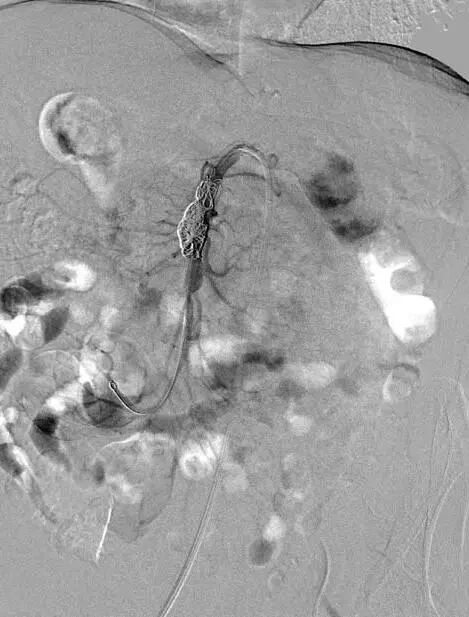

患者取仰卧位,双侧腹股沟区消毒铺单后局麻下分别经双侧股动脉穿刺置入7F(右侧)/5F(左侧)血管鞘组,予40mg肝素钠静脉注射全身肝素化,先经左股动脉插入4FRH导管,将导管头端置于肠系膜上动脉开口处,注入对比剂行肠系膜上动脉IADSA;再经右侧股动脉插入7F长鞘至肠系膜上动脉开口,旁路加压滴注生理盐水;明确病情后选取工作角度,先经4FRH导管路途下同轴送入1.7F栓塞微导管,旁路加压滴注生理盐水,经微导丝配合将其头端至于肠系膜上动脉夹层囊状动脉瘤腔内,于动脉瘤填入5枚弹簧圈行夹层动脉瘤弹簧圈填塞术;经右侧股动脉长鞘入路沿导丝送入1枚支架(SmartFlex 6mm×80mm,USA)该支架具有可预见的近端定位+参考Marker,准确定位后行肠系膜上动脉真腔成形术,支架覆盖夹层段。复行肠系膜上动脉IADSA示:支架位于肠系膜上动脉主干夹层段,支架覆盖夹层动脉瘤出入破口,支架内血流通畅,分支血管显影良好,支架以远血管主干及分支显影较术前增多增浓,多发夹层动脉瘤腔内弹簧圈均匀填塞。手术结束,使用Exoseal封堵止血系统闭合双侧股动脉穿刺点。

夹层动脉瘤内弹簧圈栓塞

支架释放

术后造影图像